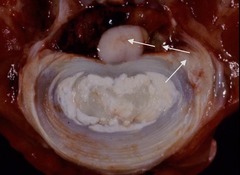

Endocardiosis

Front

Back